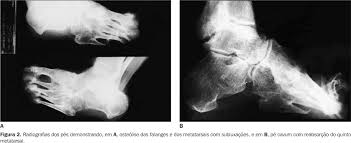

Osteólise Essencial

O Osteolysis das maxilas foi relatado em colaboração com a infecção, os quistos, a neoplasia, e o metabólico, glândula endócrina, ou anomalias hematológicas. Os casos raros do osteolysis idiopático foram gravados igualmente. Nós relatamos o exemplo de uma menina dos anos de idade 10 com resorption básico e alveolar mandibular do osso que continuou durante 9 anos. O paciente desenvolveu subseqüentemente o resorption bilateral do rami e dos côndilos de ascensão. O maxilla é uninvolved. As investigações incluíram a radiologia, o tomography computarizado, o scintigraphy, a hematologia, a química do soro, a endocrinologia, a histopatologia, a microbiologia, e a imunologia. O chemotaxis do neutrófilo, a quimioluminescência, e os valores aleatórios da migração eram baixos mas dentro da escala normal. Estes resultados são interpretados como a indicação de uma variação incomun do osteolysis maciço.